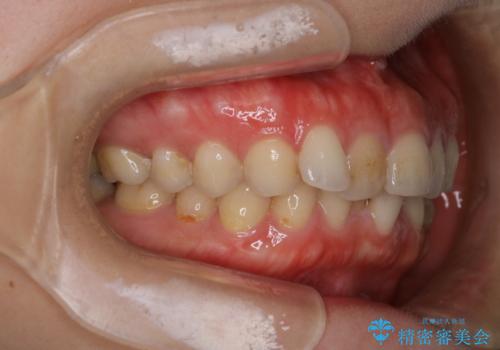

- 下顎前歯の叢生を主訴に来院されました。

臼歯関係の状態から下顎前歯一本の抜歯を行う治療計画を立て、インビザラインを使用して治療を行いました。

今回の抜歯ケースはインビザラインでも綺麗に治ります。